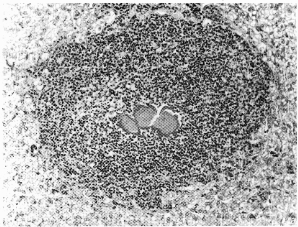

Figure 3. Eosinopbilic abscess (MKbody) in

the liver of a ferret. The Splendore-Hoeppli

reaction at the center of the lesion

surrounds a degenerating microfilaria

x2O0).